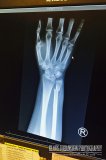

Sunshine Coastin ainoa sairaala sijaitsee Secheltissä, noin 60 kilometriä Egmontista takaisin kohti Vancouveria. Ajomatka kesti tunnin, mutta perillä pääsimme nopeasti ensiapuun ja röntgenkuvat vahvistivat että pienempi ranteen kahdesta luusta oli todellakin napsahtanut kokonaan poikki. Todennäköisesti kaatuessa rannekello oli painanut luuta ja aiheuttanut luun täydellisen katkeamisen. 💡

Röntgenkuva ranteesta

Lääkäri laittoi Niinalle ranteen mittaisen kipsin ja kertoi että luut kyllä parantuisivat asentoonsa 4-6 viikossa. Tieto oli rauhoittava ja luulimme pahimman olevan jo takanamme. Onneksemme saimme ottaa röntgenkuvasta valokuvan, jonka Niina laittoi illalla Facebookiin. Siellä Suomessa asuva lääkärituttava kuitenkin totesi, että kyseisen luun parantuminen vaatisi hänen mielestään paljon pidemmän kipsin ja että Suomessa yleensä vielä ranneleikkauksen, jotta voitaisiin varmistua siitä että ranne tosiaan luutuu oikealla tavalla.